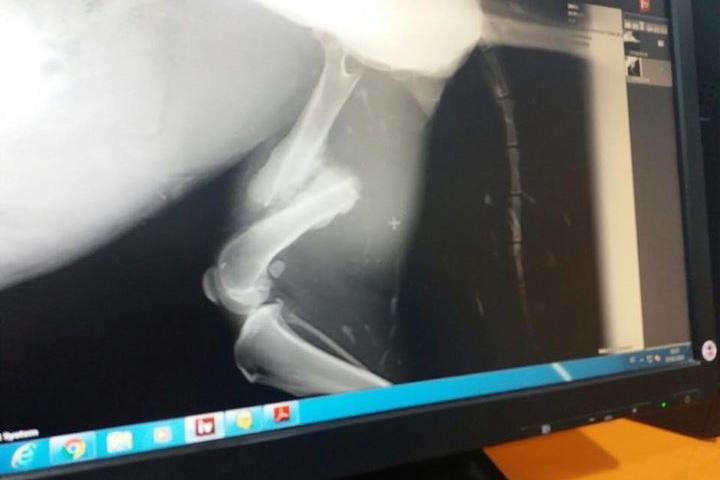

Lara-Border Collie con desprendimiento de retina y pata fracturada

Border Collie rescatada en muy mal estado. Ha perdido un ojo, tiene desprendimiento de retina y el hueso de una pata de atrás fracturado. Hay que operarla. La operación nos cuesta 773,98 euros. Necesitamos toda la ayuda posible para pagar la factura y para difundir a esta peque, y que encuentre pronto una familia que la quiera como se merece y pueda olvidar su pasado. Para realizar donaciones: Unicaja: ES55 2103 0459 03 0010008917 Titular es Qualidice, Protectora de Herencia Concepto: Ayud